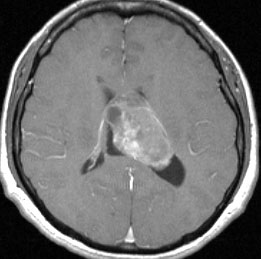

20代の男性の神経細胞腫です。側脳室の中のとても大きな腫瘍です。上段はガドリニウムという造影剤を入れた時のMRIです。下段の中央はCTですが,石灰化が見られます。脳外科の先生には,この脳室内腫瘍は一見transcallosal approach(経脳梁到達法)という手術で取れるように見えるかもしれませんが,そうではなくて,脳室の壁とくに上壁と側壁にくっついているのでなかなか取れません。この患者さんの場合は右の頭頂葉というところからtranscortical approach(経皮質到達法)で全摘出しました。後遺症もなく再発もなく術後10年が過ぎています。全部とれれば治ってしまう腫瘍です。